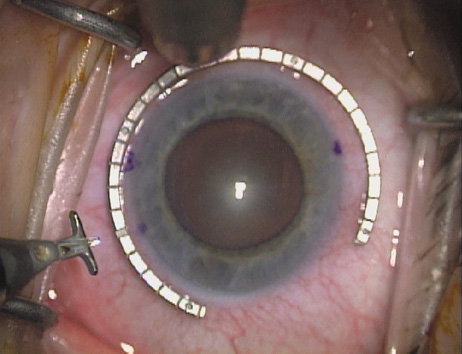

All incisions are paired, except in the case of very low ATR astigmatism wherein a single 35-degree nasal LRI is placed opposite to the single-plane temporal clear-corneal phaco incision. Paired incisions are preferred to optimize symmetric corneal flattening and are expressed in degrees of arc rather than chord length. This is done in order to diminish over- and undercorrections for unusually small or large corneas, because corneal diameter may significantly impact the relative length of the arcuate incision and its resultant effect (Fig. 3). This nomogram, which has been designed specifically for the cataract patient, is based upon the use of an empiric blade depth setting of 600 microns. Individual surgeon technique and blade style may impact results, and thereby require adjustment of the nomogram. A second, slightly more aggressive nomogram is used with younger patients, particularly in the setting of refractive lens exchange surgery or in conjunction with LASIK for the correction of higher levels of astigmatism (Table 2). In this setting where optimal precision is mandated, pachymetry is performed over the entire arc length of the intended incision site, and a diamond blade with an adjustable micrometer is set to 90% of the thinnest reading obtained. The NAPA nomogram, pachymetry, and adjusted blade depth settings may certainly be used with the cataract patient, but the small compromise that is made in using an empiric blade depth setting is felt to be acceptable in this older patient population in light of increased OR efficiency.

The extent of arc to be incised may be demarcated in several different ways. Our preferred method makes use of a modified Fine-Thornton fixation ring (Nichamin Fixation Ring and Gauge; Mastel Precision, Storz, Rhein Medical). This instrument serves to fixate and position the globe in order to optimize incision placement, as well as to delineate the extent of arc to be incised. One visually extrapolates from the limbus to marks on the surface of the ring. Each incremental mark is 10 degrees apart, and bold hash marks (180 degrees) opposite to each other serve to align and center the incision over the steep meridian. This approach obviates the need to ink and physically mark the cornea. If one desires, particularly when first gaining experience with LRIs, a two-cut RK marker may be used to place ink marks upon the cornea to show the exact extent of arc that is to be incised, in conjunction with the fixation ring/gauge (Fig. 4). Alternatively, various press-on markers are available, such as those made by Rhein Medical (Dell-Nichamin Marker, Nichamin-Kershner Marker, or the Ruminson Marker) (Fig. 5). ASICO and other instrument companies offer a full line of dedicated markers, rings, and blades for performing LRIs.

Fig. 10. The single footplate diamond blade is inserted perpendicular to the corneal surface and at the peripheral most extent of clear corneal tissue. In this case, the nomogram calls for arcuate incisions of 45 degrees. Therefore, the incision is begun approximately 22.5 degrees to one side of the broad hash mark. (Reprinted from Hardten DR, Lindstrom RL, Davis EA. Phakic Intraocular Lenses: Principles and Practice. Thorofare, NJ: SLACK Incorporated, 2004, with permission.)

Fig. 22. A second mark is made delineating the opposite extent for a total arc length of just under 60 degrees.